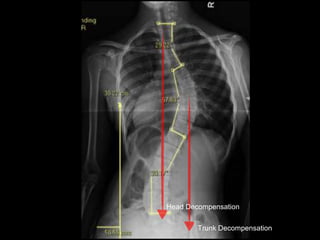

• Decompensation - Head/Trunk

Head Decompensation

Trunk Decompensation

14+6y old girl who is 18 months postmenarchal

with right sided thoracic scoliosis,

probably adolescent onset idiopathic,

with trunk decompensation but without head

decompensation,